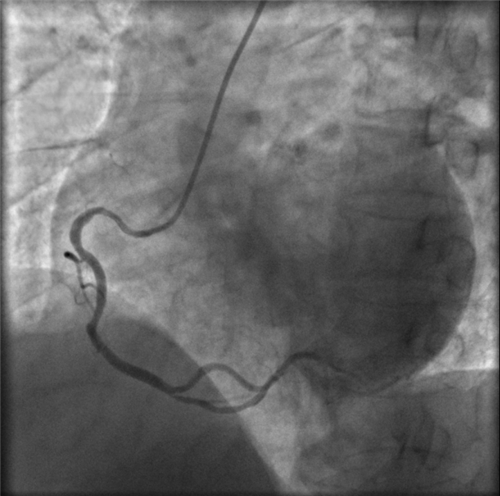

右冠近段嚴(yán)重狹窄,未見(jiàn)右向左的側(cè)枝循環(huán)

再行右冠造影,右冠近段也嚴(yán)重狹窄,未見(jiàn)右冠向左冠的側(cè)枝循環(huán)。